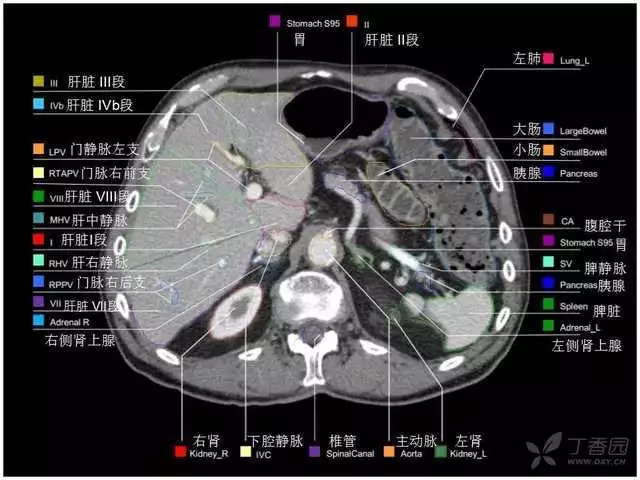

腹部肝脏高清CT断层的图谱

全腹部高清CT图谱,淋巴结彩色图谱,血管解剖图谱大汇总!